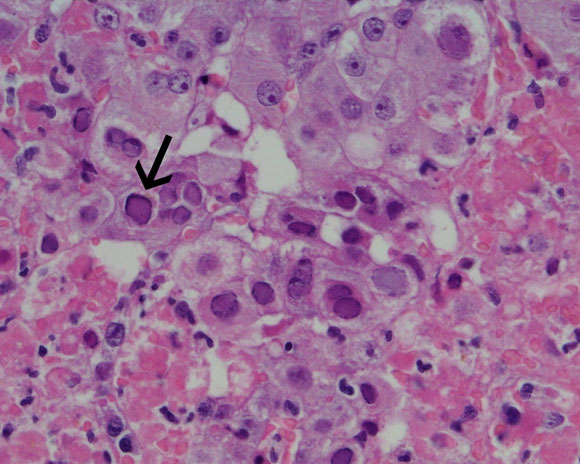

Liver biopsy, precluded by coagulopathy during the caesarean section, was accomplished on Day 13. Histology revealed hepatic necrosis, with 40%–50% of the hepatic parenchyma showing haemorrhagic necrosis with a neutrophilic infiltrate (Box 1A). At the interface between necrotic areas and surviving parenchyma, many liver cells showed glazed amphophilic chromatin consistent with herpesvirus inclusions. Polyclonal herpes simplex virus immunoperoxidase stain showed strong nuclear staining in these cells (Box 1B). Polymerase chain reaction testing of her serum subsequently revealed herpes simplex virus (HSV) DNA and HSV 2 was cultured from a vaginal swab.